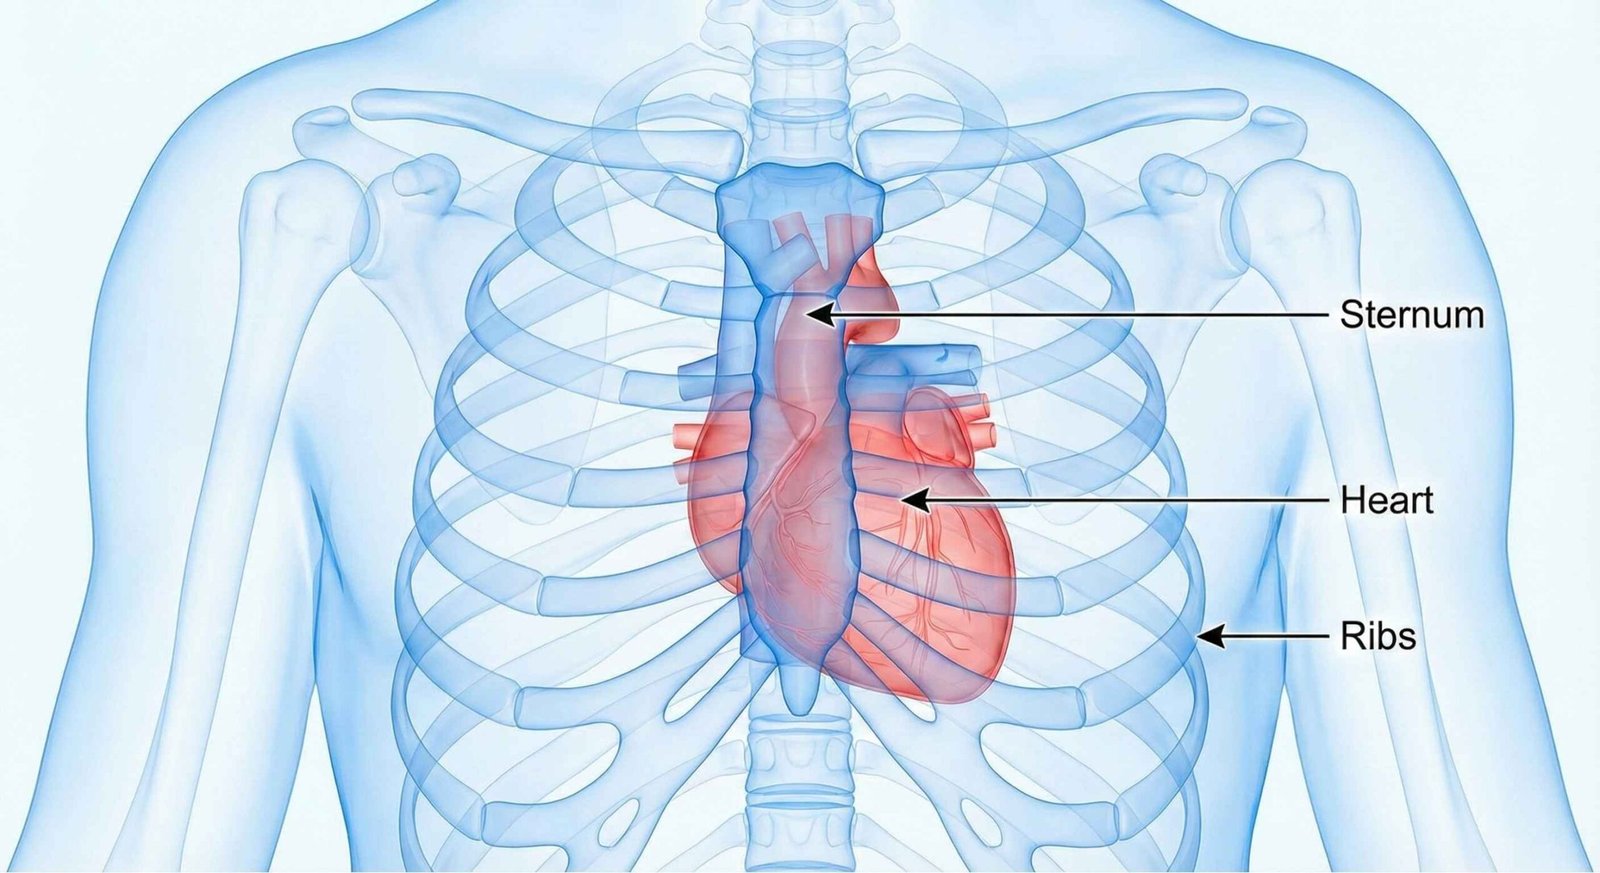

Understanding the Anatomy of Chest Pain

To understand your chest pain, it helps to know where it is coming from. The chest cavity contains vital organs like the heart and lungs, but also the esophagus, muscles, nerves, and bones.

What is Retrosternal Chest Pain?

Retrosternal chest pain refers to discomfort felt directly behind your breastbone (sternum). This type of pain is often a significant concern because it is a classic symptom of a heart attack. However, it can also originate from the esophagus.